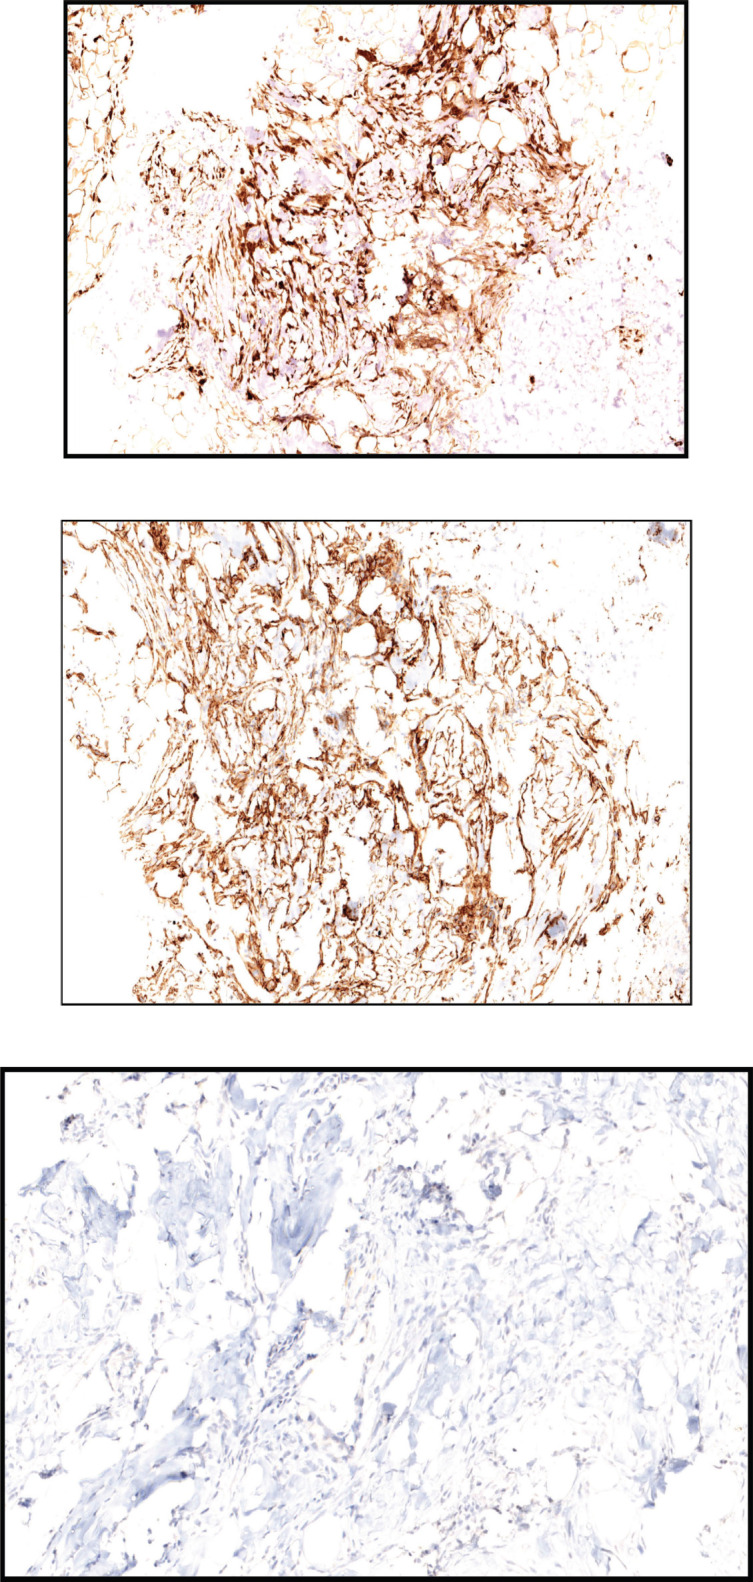

With the advent of next-generation sequencing, increasingly we can sub classify the soft tissue sarcomas into various subtypes with distinct prognostic and therapeutic implications. Sarcomas with RAF1 mutations are extremely rare and so far, the treatment strategies are not known. Here, we report a case of a 48-year-old lady who initially presented with right ear swelling, which was excised and was suggestive of dermatofibrosarcoma protuberans with S100 expression. After a disease-free interval of 25 months, the patient relapsed with metastasis in the lung. Repeat biopsy and next-generation sequencing (NGS) were suggestive of PDZRN3/RAF1 fusion mutated sarcoma. On presentation, the patient had an Eastern Cooperative Oncology Group performance status of 4 and had respiratory distress due to lung metastasis. After consensus and decision in the molecular tumour board, the patient was started on low-dose trametinib and doxorubicin. After three cycles of treatment, the patient had a partial response and post six cycles she had a near-complete response. This case exemplifies the value of molecular characterisation of soft tissue sarcoma and adds to the already sparse literature for RAF1 mutated sarcomas.

Abstract Image